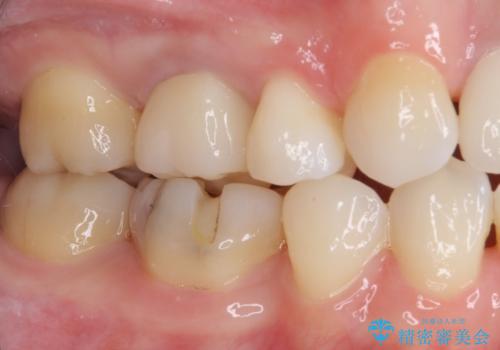

自然に仕上がり、患者様には大変満足していただきました。